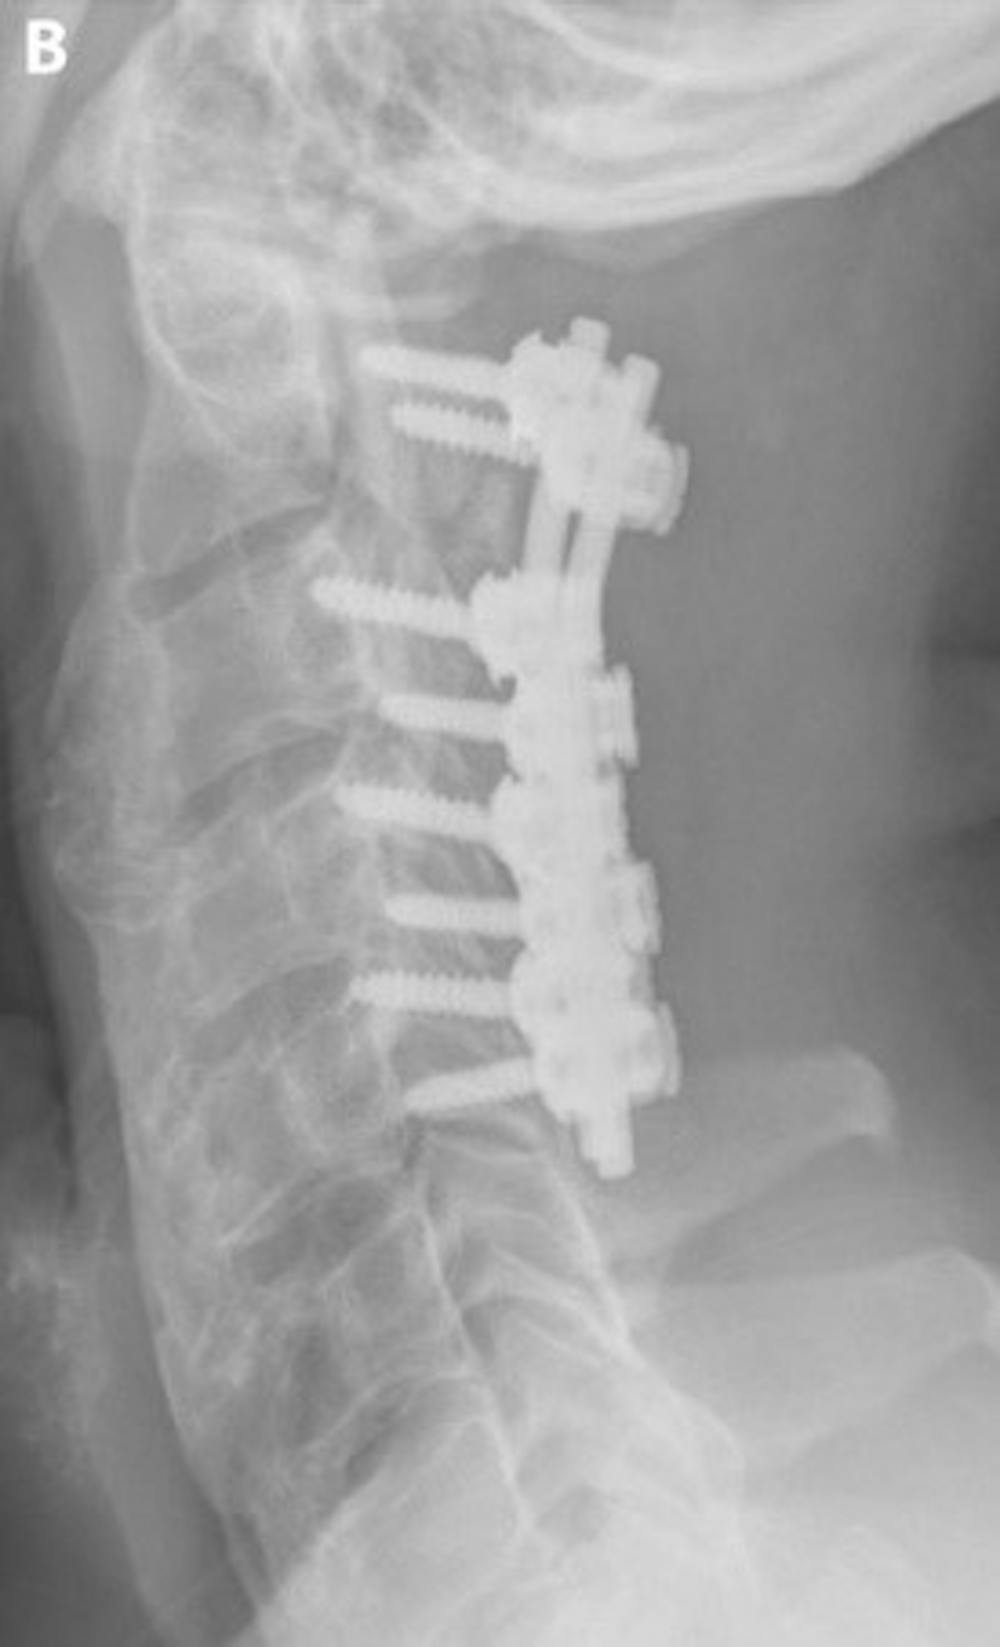

B) 術後頸椎外側 X 光片顯示椎板切除術(切除構成椎管後部的骨頭)和用側向品質螺釘和桿穩定頸椎的儀器。 椎板切除術可有效增加椎管的大小。